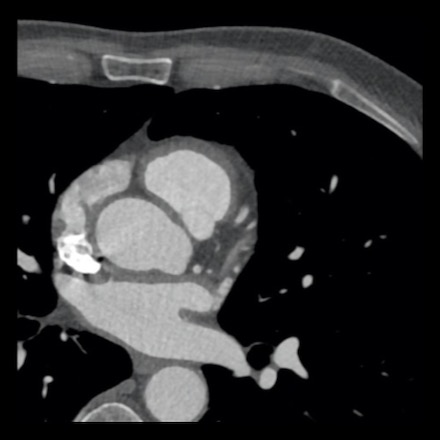

case 2 – CAD-RADS 5/P2/S

First, scroll through the CTA images.

How would you describe the findings on the coronary CTA?

The findings are:

- Stent in the mid

LAD with low-attenuation within the stent suggestive of minimal in-stent

restenosis (<25%). Non-calcified plaque distal to the stent

causing mild stenosis (25-49%). Notice bridging on a short segment in

the distal LAD. - Non-calcified

plaque in the LCX causing mild stenosis (25-49%). - Occlusion of the

proximal OM1 branch with distal filling. - Calcified and

non-calcified plaques in the proximal RCA causing mild (25-49%) stenosis. - Total plaque burden

is moderate based on SIS (four segments including proximal RCA, mid LAD, prox

LCX and OM1).

Due to the occlusion of OM1 branch and presence of the stent, this case

reads as CAD-RADS 5/P2/S, which means that this patient needs further

diagnostic workup.